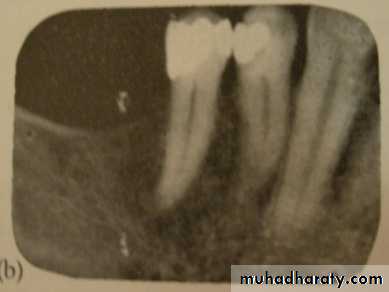

• Radiographs

• A complete series of periapical and bitewing radiographs is essential for complete examination.• Panoramic radiographs are ideal for screening for pathologic conditions.

• Excellent periapical radiographs are essential for determining the crown/ root ratio of the remaining teeth, the status of periodontal ligament space, and lamina dura, quality of ridge in the edentulous areas.